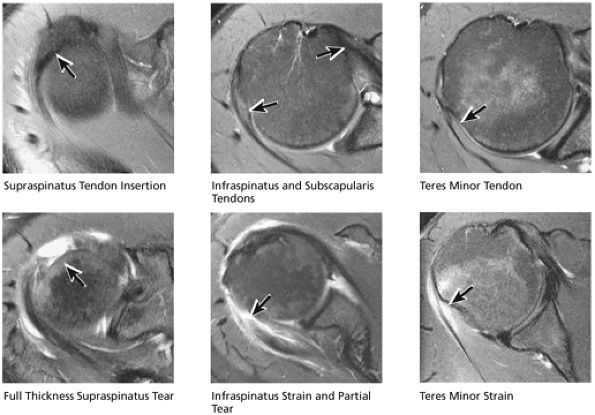

FIGURE 8.32 Rotator Cuff.